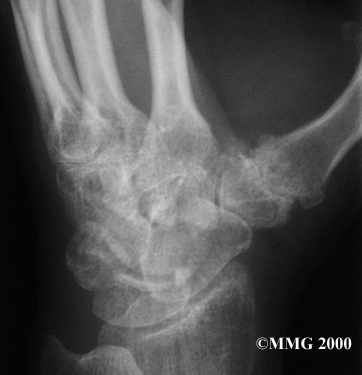

The CMC joint (an abbreviation for carpometacarpal joint) of the thumb is where the metacarpal bone of the thumb attaches to the trapezium bone of the wrist. This joint is sometimes referred to as the basal joint of the thumb. The CMC is the joint that allows you to move your thumb into your palm, a motion called opposition.

Carpometacarpal Joint

Trapezium Bone

Your doctor may take X-rays to see how much the joint is damaged.

X-Rays

This test usually determines how bad the degenerative arthritis has become. How much articular cartilage remains in the joint can be estimated with the X-rays.